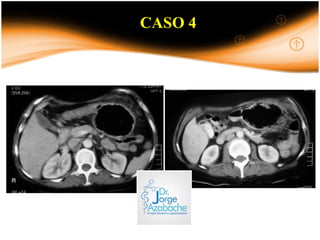

CASO 4

Paciente mujer de 48 años que presenta dolor abdominal de 15 días

de evolución asociado a distensión y nauseas. Elimina gases por

colostomia.

Es portadora de colostomía por cirugía de vólvulo de sigmoides

hace 3 meses.

EXAMEN FISICO

FR: 20 x’ P: 84 x’ Tº: 36 °C PA:120/60

AGP: Paciente despierta, OTEP, AREG.

TÓRAX: Buen pasaje de MV en ACP, no rales.

ABDOMEN: Distensión ++/+++, RHA (+) muy disminuidos en

frecuencia, B/D, no signos de irritación peritoneal.

Colostomia: permeable.

TR: N/E

D P